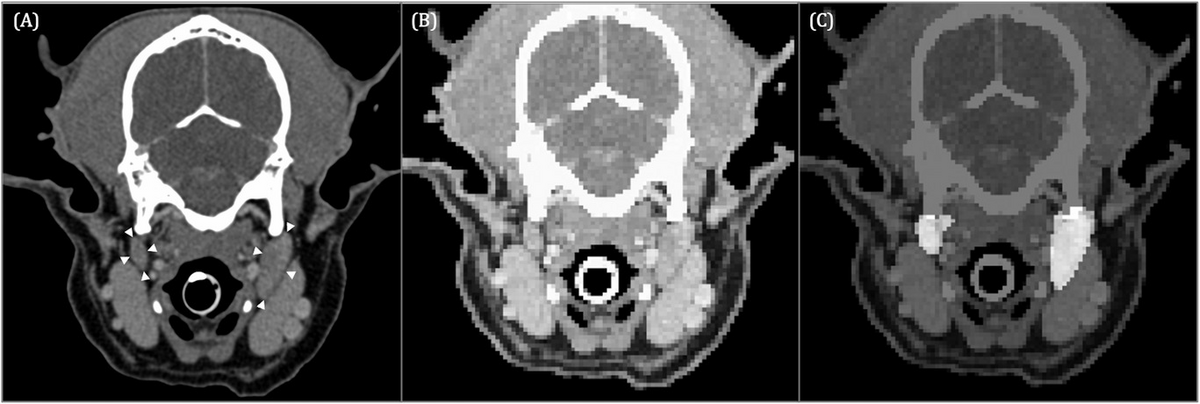

AI can segment medial retropharyngeal LNs

VRU 63(6): 763-770